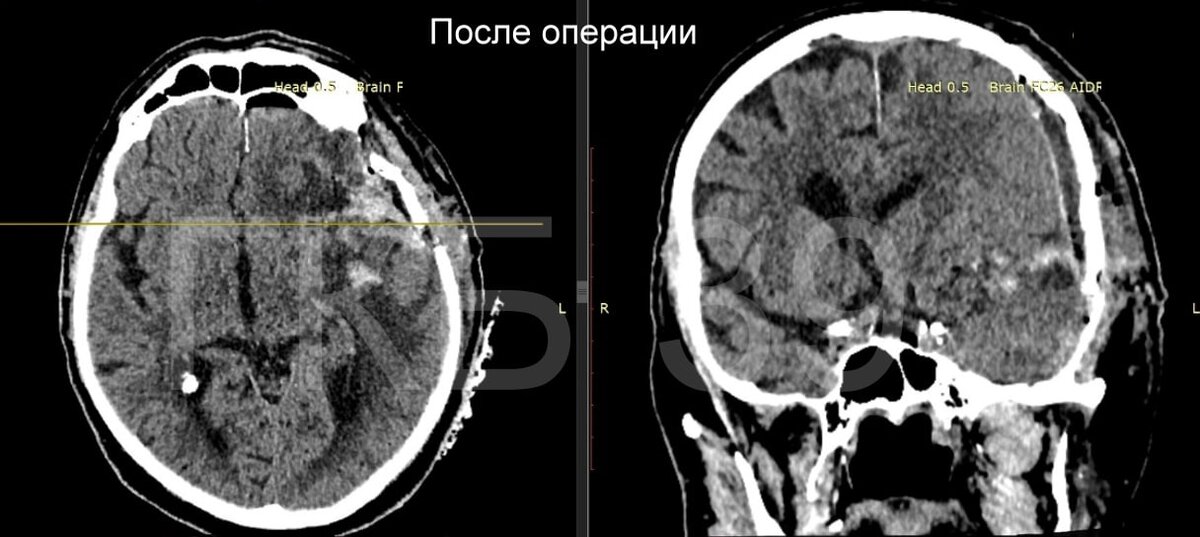

10-сантиметровая опухоль занимала почти треть левого полушария мозга. Она сдавливала лобную, височную и теменную доли и смещала мозг.

Заведующий 1-м нейрохирургическим отделением ГКБ №39 Александр Лавренюк и нейрохирург Сергей Гришин 4,5 часа оперировали мужчину. Через 10 дней его выписали домой в удовлетворительном состоянии. Опухоль оказалась доброкачественной, и мужчина смог вернуться к полноценной жизни.